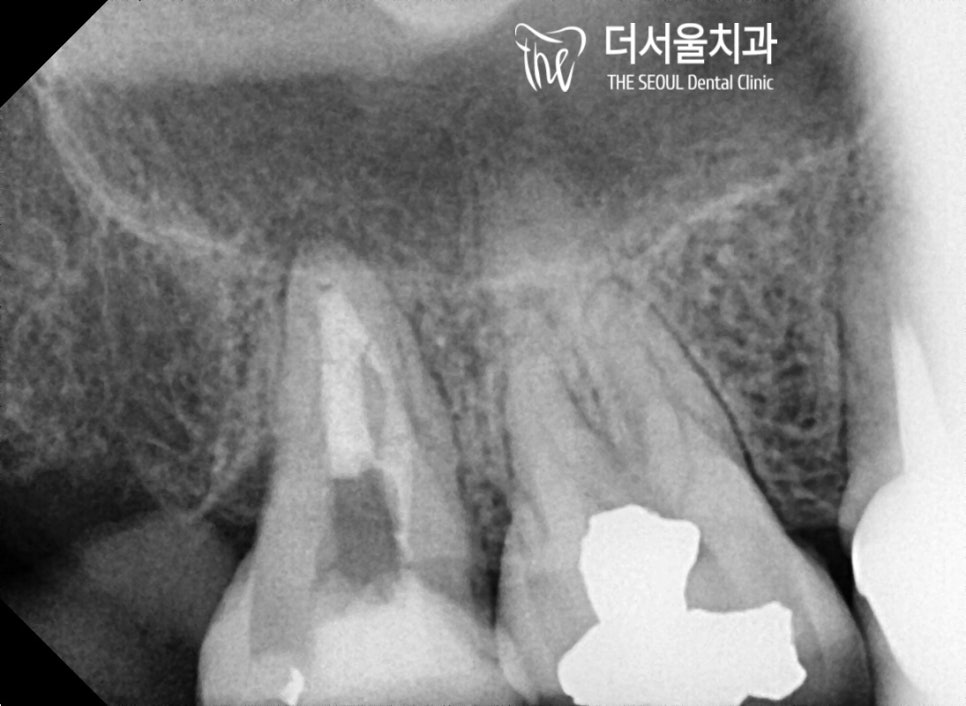

좀 더 자세히 살펴보기 위해

파노라마 촬영을 진행한 결과.

단 몇 개월이라도 일찍 내원을 하셨더라면

이런 일까지 벌어지지 않았을 텐데..

참 아쉬움이 드는 건 어쩔 수 없나 봅니다 ㅎㅎ

『박원장의 계획』

이런 경우에는..

어쩔 수 없이 신경치료 를 통해

감염된 치수를 제거, 세척하고

새로운 충전재를 사용하여 채워 넣어야 됩니다.

뭐 여기서 상황이 더 악화되면

발치 후 임플란트를 심어야 될 수밖에 없죠.